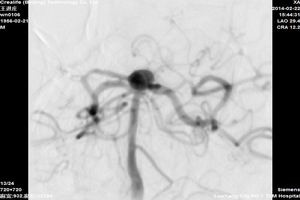

主要开展急性脑梗死溶栓、取栓,颈动脉狭窄支架植入、颅内脑血管狭窄支架植入、动脉瘤栓塞,脑出血微创穿刺血肿清除术。

基地动脉尖动脉瘤术前 基底动脉尖动脉瘤术后